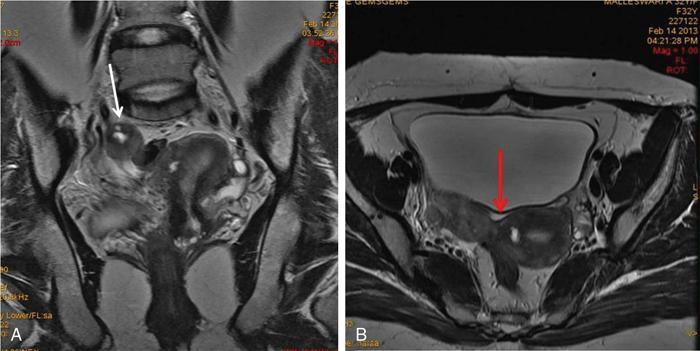

MÜLLERIAN DUCT ANOMALIES Rajani Gorantla Müllerian ducts are a pair of tubular structures that give rise to uterus, cervix, fallopian tubes and upper two-thirds of vagina. Disruption or failure of normal development can result in occurrence of Müllerian duct anomalies (MDAs). These are commonly associated with other congenital anomalies of urinary tract and ovaries due to the close relationship between the development of mesonephric and paramesonephric ducts; few patients also have associated skeletal system anomalies. The prevalence of MDAs in an unselected population was 5.5%; 8% among the infertile women, 12.3% in women with a history of recurrent pregnancy loss and 24.5% in women with miscarriage and infertility. Most of the patients with MDAs are asymptomatic and found incidentally on imaging for any other gynaecological problems, in evaluation of a patient with renal, skeletal or abdominal wall abnormalities. In symptomatic women, complains are related to the type, severity, obstructive anomaly or nonobstructive anomaly. The symptoms can be obstetric or gynaecological related, includes recurrent spontaneous abortions, infertility, preterm labour, intrauterine growth restriction and abnormal foetal lie. Few adolescent girls may present with primary amenorrhoea, hypomenorrhoea, abnormal vaginal bleeding, cyclical pain and mass. Rarely they can present with pelvic inflammatory disease with abnormal vaginal discharge, dyspareunia and urinary tract infections. The female reproductive system develops from a pair of Müllerian or paramesonephric ducts, urogenital sinus and vaginal plate. The ovaries develop separately from the primordial ridge. It is of great importance to understand the normal stages of development, as failure or interruption of any of these stages can lead to a simple to complex spectrum of anomalies. The three stages of Müllerian duct development include: At 6–10 weeks of gestation age, two paired Müllerian ducts and Wolffian ducts formation occurs. When Y chromosome factor (testicular determining factor) is absent, the Wolffian ducts undergo degeneration. The Müllerian ducts further elongate caudally and cross the Wolffian ducts to fuse in the midline. At 10–13 weeks of gestation age, caudal and lateral fusion of the two Müllerian ducts forms primitive uterovaginal canal, which is possessed of solid tissue initially located side by side and further internal canalization leads to the formation of two channels/canals divided by a septum. At this stage, there is reabsorption of the caudal septum and forms single cervical canal and vagina lumen. In around 15–20 weeks of gestation age, complete resorption of the septum takes place in a caudocranial direction from the isthmus to fundus and development of single endometrial cavity results. The fused caudal part of Müllerian ducts gives rise to the uterus, cervix and upper two-thirds of vagina; the unfused cranial part forms the fallopian tubes (Fig. 11.14.1.1). The lower vagina develops from the urogenital sinus, which is separated from the rectum by urorectal septum around 7 weeks of gestation age. The primitive uterovaginal canal embeds into the dorsal wall of urogenital sinus and forms Muller’s tubercle. Around 13 weeks of gestation, two solid masses known as sinovaginal bulbs originate from the upper part of the Muller’s tubercle, further proliferate into the caudal end of the uterovaginal canal to become a solid vaginal plate. Later canalization or degeneration of the central cells of the vaginal plate forms the lower vagina, which is usually completed by 20 weeks’ gestation. The vertical fusion of the upper and lower vagina occurs with resorption of tissue in between and forms single vaginal cavity (Fig. 11.14.1.2). The vaginal lumen is separated from the urogenital sinus by the hymenal membrane. Just before birth, the hymen normally ruptures due to retrogression of the central epithelial cells. However, a thin fold of mucous membrane persists around the vaginal introitus. The ovaries develop separately from migration of primordial germ cells to the genital ridge. Ureteric buds develop separately and concurrently. So renal anomalies are most commonly associated with MDAs with an association of 30%–50%. Various classification systems have been proposed over the past several decades to describe MDAs. Ideally, same classification system needs to be followed by a gynaecologist, surgeon and radiologist for better communication. Buttram and Gibbons classification was suggested in 1979, and it was based upon the level of failure in normal development and segregate the anomalies into groups with similar clinical manifestations, treatment, and prognosis for foetal salvage. According to Buttram and Gibbons, the uterine anomalies were classified into six classes as described in Table 11.14.1.1. The drawback is the lack of classification of vaginal and other anomalies separately. The ASRM (previously the American Fertility Society – AFS) classification system is the most widely accepted classification worldwide over the past years and was introduced in 1988. According to this classification, MDAs are classified into seven classes (class I to class VII) as mentioned in Table 11.14.1.2. However, several limitations have been described by Grimbizis and Campo in 2010 (Fig. 11.14.1.3). The drawbacks of the ASRM classification system are as follows: Hence in 2016, an updated classification of uterine septum, that is ASRM-2016 was proposed and officially approved morphometric criteria are given for distinguishing between septate, normal/arcuate and bicornuate uteri (Table 11.14.1.3). The VCUAM classification was proposed in the year 2005. The main concern is to provide a simple, systematic, clinical classification in addition to providing a precise reflection of the entire malformation. The female genital organs were divided into the following subgroups in accordance with the anatomy: vagina (V), cervix (C), uterus (U) and adnexa (A). Associated malformations were assigned to a subgroup (M) relative to each specific organ. The disadvantage is due to its inherent complexity, and more than 56,700 individual combinations of anomalies are possible. ESHRE and ESGE established a common working group named CONgenital UTerine Anomalies (CONUTA) in order to devise an improved classification system (Table 11.14.1.4). It was published in 2013. Anatomy is the basis for systemic categorization of the MDAs. The subclasses are divided by the different degrees of uterine deformity and their clinical significance (Fig. 11.14.1.4). Cervical and vaginal anomalies are classified into independent supplementary subclasses (Figs. 11.14.1.5–11.14.1.6). For most of the clinicians, it helped as starting point for the development of guidelines for their diagnosis and treatment. The malformations are graded according to severity, U0–U5, C0–C4 and V0–V4, with U5, C4 and V4 being more severe. Class U3 incorporates bicorporeal fusion defects (didelphys and bicornuate) as this was considered as a more functional mode of classification. Arcuate uterus was not included separately, but this is categorized under normal variant into class U1c. Recent studies have demonstrated that the ESHRE/ESGE system provides an effective and comprehensive classification for almost all the currently known MDAs and overcomes the limits of previous classifications. However, there is a relative overdiagnosis of septate uterus with the application of ESHRE–ESGE criteria has been reported and which potentially might lead to unnecessary surgical overtreatment. C0 C1 C2 Normal cervix Septate cervix Double ‘normal’ cervix C3 C4 Unilateral cervical aplasia Cervical aplasia U4 V0 V1 V2 V3 Normal vagina Longitudinal nonobstructing vaginal septum Longitudinal obstructing vaginal septum Transverse vaginal septum and/or imperforate hymen V4 Vaginal aplasia C MDAs’ characterization and classification is of great significance, as the treatment is determined by the type and severity of abnormality. The various imaging modalities available include: HSG was the most recognized imaging modality, earlier to the development of the ultrasonography (USG) and MRI. It is an invasive fluoroscopic-guided procedure for uterine and tubal assessment, and is performed during the midproliferative phase of the cycle, ideally between days 7 and 10 of the cycle when endometrium is thin. Fluoroscopic spot images obtained to evaluate uterine configuration, uterine filling defects and fallopian tube patency. HSG allows evaluation of only the component of the uterine cavity that communicates with the cervix. The anatomic information about myometrium and external fundal contour will not be provided by HSG. The diagnostic criteria used to diagnose MDAs on HSG include: HSG findings of different MDAs are described in Table 11.14.1.5 and Fig. 11.14.1.10. Virtual HSG is a noninvasive technique performed by using a computed tomography (CT) scanner, done 45 s after the contrast material instillation begins. Contraindications are similar to those for HSG and include pregnancy and active pelvic infection. There is no necessity for retraction of the uterus or manipulation of the cervix. The procedure is quick, easy and prophylactic administration of antibiotics is not required. The use of a power injector helps to ensure a steady low pressure of instillation. The procedure is less painful, more comfortable and easily tolerated by patients than conventional HSG. Radiation exposure sometimes requires cervical clamping, which may result in complications such as bleeding and infection. Transabdominal pelvic ultrasound can diagnose uterine anomalies with accuracy rate of 47%. Two-dimensional transvaginal ultrasound (TVUS) has high sensitivity and specificity than transabdominal study and provided some information about external and internal fundal contours. The detection rate is high if the scan is performed in secretory phase due to better visualization of endometrium. Three-dimensional USG shows great accuracy than 2D USG in evaluation of the uterine morphology. The technique of 3D USG varies with different vendors. It displays both the external and internal fundal contours and lower uterine segment by acquisition of single coronal view of uterus (c-view) (Fig. 11.14.1.11). The only disadvantage is that it is transvaginal study and shall not be done in paediatric age group and sexually inactive women. Three-dimensional TVUS has become the first line of screening tool in most of the infertility clinics as it is noninvasive, faster, repeatable, allows storage of volume data and has multiplanar capability for systematic evaluation of the uterine and cervical cavities. The salient features of various Müllerian anomalies on 3D USG are described in Table 11.14.1.6 with images. Three-dimensional ultrasound is combined with sonosalpingography in this technique and provides better delineation of the uterine morphology. It is a less invasive procedure done in proliferative phase with instillation of saline into the uterine cavity and assessment of the uterus will be done. MRI is a universally accepted imaging modality in the documentation of MDAs and accuracy rate of 100% have been reported. MRI provides excellent delineation of both the internal and external uterine anatomies. T2-weighted (T2W) images are the mainstay of pelvic imaging and are performed without fat suppression. T1-weighted (T1W) images are mainly for the haemorrhagic content. The disadvantages of MRI include time-consuming procedure, not cost-effective, large body habitus, pacemakers, recent surgical history and claustrophobia. The current and proposed MRI protocol given by the European Society of Urology (ESUR-MRI protocol) intends a dedicated evaluation of MDAs as mentioned below (Fig. 11.14.1.12): Vaginal anomalies can be accurately diagnosed with the prior administration of the ultrasound gel, to distend vagina (Fig. 11.14.1.13). It will help in better diagnosis of complex vaginal anomalies, like vaginal septations or vaginal duplication. The normal MRI appearance of uterocervical canal and vagina are shown in Fig. 11.14.1.14. Uterine aplasia/hypoplasia/agenesis is class 1 MDA according to ASRM classification and U5 uterine anomaly according to ESHRE classification. It is a formation defect of the paramesonephric ducts with complete or segmental agenesis of uterus and vagina. The incidence rate is around 10%–15% of all MDAs and considered as the most severe form of uterine anomaly. Most of them have complete uterovaginal agenesis with no single completely developed uterine cavity and are associated with Mayer–Rokitansky–Küster–Hauser syndrome (MRKHS). Two types of this syndrome are depicted. The typical form or type A represents the absence or remnants of the uterus, cervix, upper two-thirds of vagina with normal ovaries and fallopian tube (Fig. 11.14.1.15). The atypical form or type B is associated with the abnormalities of the ovaries, fallopian tubes and genitourinary system (Fig. 11.14.1.16). In a few cases (approximately 10%), unilateral or bilateral uterine remnants and with or without endometrial cavity will be seen (Fig. 11.14.1.17). Most of them present with primary amenorrhoea due to complete uterovaginal agenesis and manifest as MRKHS. These patients have normal secondary sexual characteristics due to the preserved normal ovarian function and phenotype. If uterine remnants with functional cavity is present, will present with cyclical pain along with amenorrhoea due to cryptomenorrhoea and haematometra. USG is the first modality for identification of these anomalies, absence of uterus with normal ovaries is diagnostic. But, it is difficult to locate the uterine remnants and cavity due to small acoustic window. MRI is the gold standard and it classifies into uterovaginal agenesis and hypoplasia. If hypoplasia is identified, sagittal and axial sections are taken. These remnants are seen as T2 hypointense tubular structures, located in close relation to ovaries in the adnexa. Once we identify the uterine remnants, it is important to look for the functional endometrial cavity. These will have reduced endometrial and myometrial width. MRI can easily delineate the zonal anatomy due to its high soft tissue contrast resolution. The management of Müllerian agenesis consists of counselling for the patient and her parents. Some patients with MRKHS opt for creation of neovagina for normal sexual life. Various techniques are available. In the presence of a functional Müllerian remnant, regardless of whether it is communicating or not, medical suppression of menses can be initiated and should be followed by laparoscopic removal of the hypoplastic remnant. Unicornuate uterus or hemiuterus is defined as the unilateral uterine development and the contralateral Müllerian duct could be either partially formed or absent. It is a formation defect and the necessity to classify it in a different class than that of uterine agenesis, which is also a formation defect, is due to the existence of a fully developed functional uterine hemicavity. It is considered as class II anomaly according to ASRM classification and class U4 according to ESHRE classification. The frequency rate is around 20% of MDAs. Renal anomalies most often occur in association with unicornuate uterus and usually on the same side of uterine agenesis. Further unicornuate uterus is divided into two subclasses depending on the presence or absence of a functional rudimentary cavity in ESHRE classification: In ASRM classification, unicornuate uterus is divided into four subcategories: Mostly asymptomatic and presence of the noncommunicating uterine remnants will be identified at the time of infertility work up or caesarean section. If a functional cavity is present, the presentation is dysmenorrhoea or haematometra in an adolescent. The common obstetrics-related complications include abnormal foetal lie, intrauterine growth retardation, preterm delivery, placental abnormalities and uterine rupture. Gynaecological complications are ectopic pregnancy and endometriosis due to retrograde menstruation. On imaging, unicornuate uterus is seen as tubular and fusiform or banana-shaped structure at paramedian location, the endometrium is narrow and tapers to the apex with normal myometrial anatomy and reduced uterine volume. The rudimentary cavity or remnants are better depicted on 3D USG (Fig. 11.14.1.18) and MRI. However, MRI is superior to USG due to its high soft tissue resolution. The rudimentary cavity can communicate with main cavity or connected by fibrous band. The nonfunctioning cavity will be seen as T2 hypointense structure with loss of zonal anatomy (Figs 11.14.1.19 and 11.14.1.20), whereas the functioning cavity will show the deformed zonal anatomy (Fig. 11.14.1.21), and its complications like haematometra as T1/T2 hyperintense endometrial collection. Unicornuate uterus without rudimentary cavity does not require any procedure. But in the presence of communicating or noncommunicating rudimentary horn, surgical resection must be considered to prevent complications. Uterine didelphys is a class III MDA based on the ASRM classification and class U3b bicorporeal uterus according to ESHRE classification with an incidence rate of 5% among the uterine anomalies. It is a lateral fusion defect; results from complete failure of the Müllerian duct fusion. Two noncommunicating endometrial cavities with preserved zonal anatomy are seen with separate cervix. According to ESHRE classification, it is defined as external fundal indentation completely dividing the uterine corpus up to the level of external cervical os. It is most commonly associated with longitudinal vaginal septum in around 75% of cases. Some patients may show transverse vaginal septum and these will be obstructive or nonobstructive type. Renal anomalies are also commonly associated with uterine didelphys. Uterine didelphys is usually asymptomatic and diagnosed incidentally on pelvic examination or caesarean section. The uterine didelphys with obstructed vagina (Fig. 11.14.1.22) will present at adolescence as dysmenorrhoea, haematometrocolpos and haematosalpinx. Sometimes retrograde menstrual flow can cause endometriosis and pelvic adhesions. Obstetric-related complications include abortion/foetal growth restriction and poor pregnancy outcome. The uterine didelphys with obstructed hemivagina due to transverse vaginal septum and associated ipsilateral renal agenesis are the manifestations of the syndrome called obstructed hemivagina and ipsilateral renal agenesis anomaly/Herlyn–Werner–Wunderlich (HWW) syndrome (Fig. 11.14.1.23).